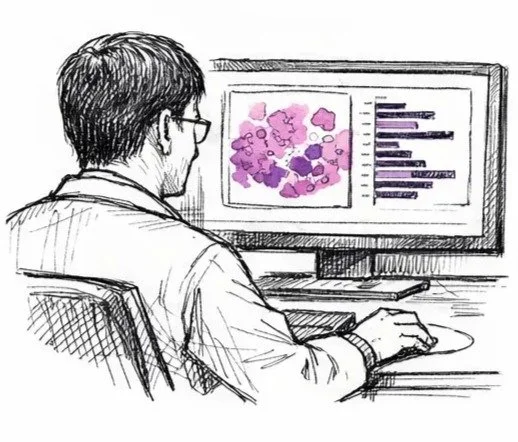

Analys

2.

Platin-DRP® använder en multigen, mRNA-baserad algoritm för att utvärdera tumörens genuttryck över 205 licensierade gener kopplade till känslighet och resistens mot cisplatin och karboplatin. Resultatet är ett kontinuerligt värde från 0 till 100, där högre poäng indikerar större förväntad nytta av platinabehandling. Lägre poäng tyder på minskad känslighet för platina.